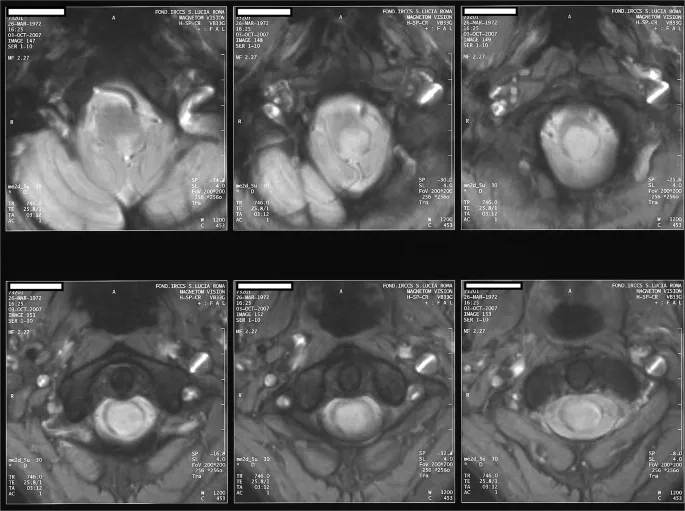

• Key syringomyelia symptoms include progressive muscle weakness and wasting, particularly in the hands, arms, and shoulders, which worsens over the years.

• Patients often experience a loss of pain and temperature sensation in a "cape-like" distribution across the back and arms, while touch sensation remains.

• Regular monitoring with MRI scans is essential to track the size and progression of the syrinx and determine the best timing for surgical intervention.